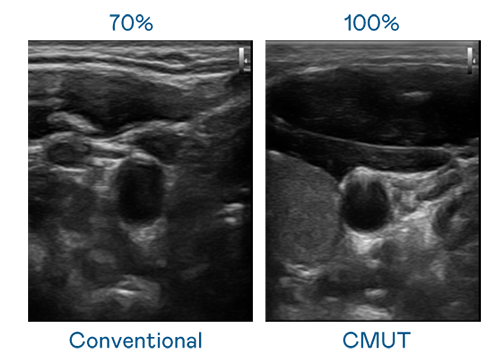

CMUT 技术是一种用电容式微机电元件来产生超音波讯号的技术。与传统 PZT 压电式技术相比,CMUT 频宽增加 30%,更宽频的超音波讯号让影像解析度大幅提升,是实现高影像品质医疗超音波扫描、促进精准医疗发展的关键技术。

超音波影像的解析度高低,首先取决于探头能发出的讯号频宽。蘑菇视频免费网站入口 CMUT 可提供高清晰的超音波讯号,提供高频宽、高灵敏度、影像纹理细节更高的超音波影像,协助医护人员缩短影像判读时间及利用精准的医疗影像进行诊断。